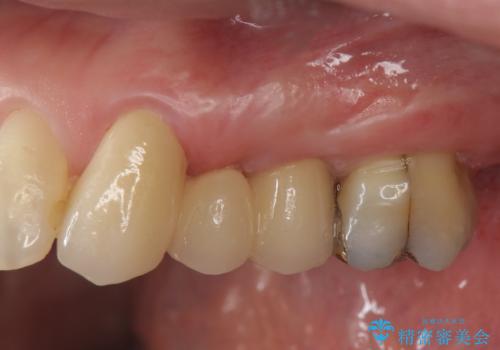

- 47.3万円(仮歯・ジルコニアクラウン×3 ・ 小矯正)費用は治療当時の料金となります

矯正を行うことで歯を適切な位置に動かすことでより、清掃性に優れ長期的な予後を見込むことのできるブリッジを製作することができました。